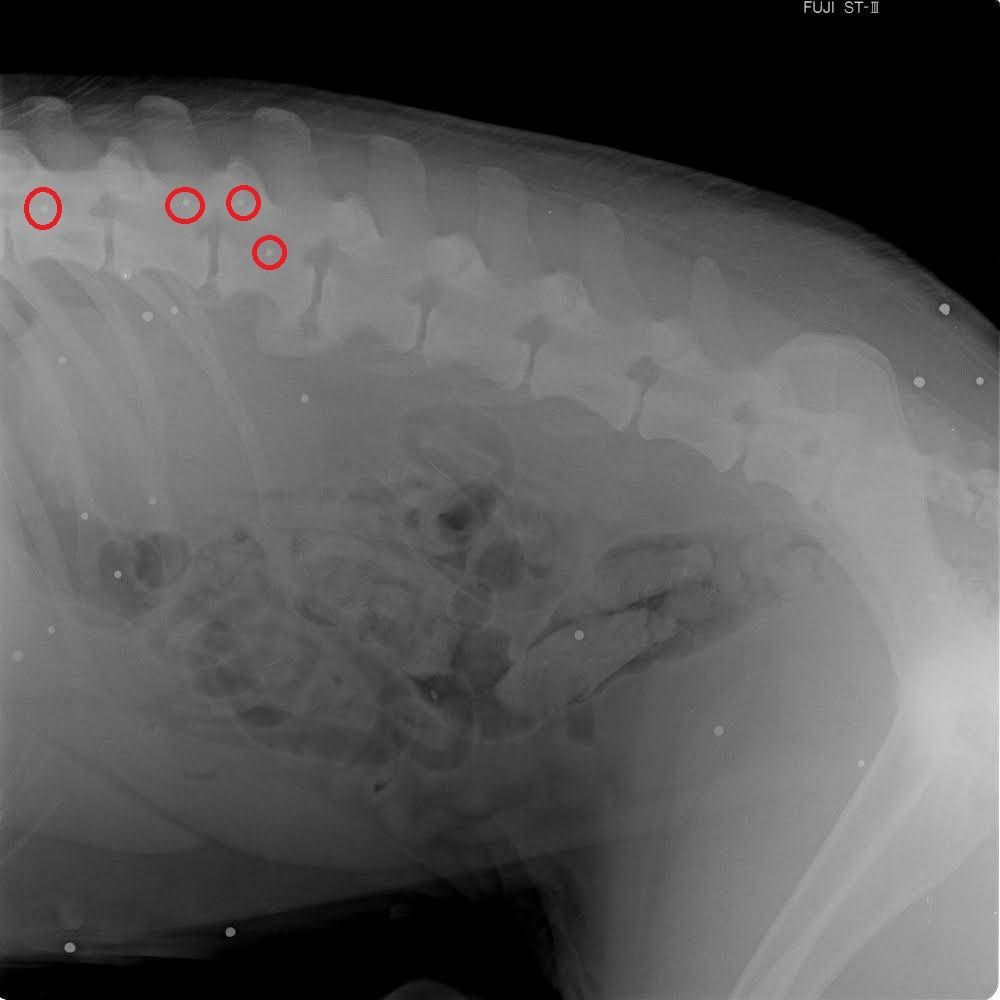

Στις εγκαταστάσεις του Φιλοζωικού Ομίλου Καλαμάτας (Φ.Ο.Κ.) φιλοξενείται ο σκύλος που ζούσε στο χωριό Κατσαρού Μεσσηνίας και είναι σχεδόν ανάπηρος, καθώς δυσκολεύεται να περπατήσει. Η αιτία της αναπηρίας του ζώου φάνηκε μόλις το πήγαν στον κτηνίατρο στις 27 Φεβρουαρίου και εκείνος του έβγαλε ακτινογραφία.

Το σώμα του σκύλου έχει σκάγια κάποια από τα οποία έχουν πετύχει τη σπονδυλική του στήλη με αποτέλεσμα το ζώο να υποφέρει από το κινητικό πρόβλημα. Ο Φ.Ο.Κ. στην ανακοίνωση του για την κακοποίηση και αυτού του σκύλου επισημαίνει τα εξής στις 28 Φεβρουαρίου: «Ο αντιδήμαρχος Οιχαλιας κος Δημοσθένης Τράγος δίνει 1000€ σε οποίον κατονομάσει τον δολοφόνο.!!!

Τα σκάγια παντού στο σώμα του σκύλου και στην σπονδυλική του στήλη.

Τα σκάγια παντού στο σώμα του σκύλου και στην σπονδυλική του στήλη.

Ήρθε κοντά μας πριν λίγες ημέρες σαν ανάπηρο αδέσποτο από τον Δήμο Οιχαλιας. Μεταφέρθηκε στον κτηνίατρο όπου διαπιστώθηκε ότι είναι περίπου 6 ετών, πυροβολημένος στην σπονδυλικη στήλη και καποια σκάγια πιέζουν τον νωτιαίο μυελό.